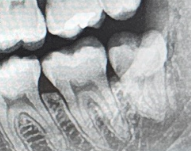

[좌측]

• 2번 째 사진

사랑니의 머리가 보인다면 잇몸 절개를 하지 않을 수도 있습니다 하지만 오른쪽 아래에 사장니의 경우에는 발치를 수월하게 하기 위해서 잇몸 절개 후에 진행을 하는 것이 더 좋을 수도 있습니다.

2 케이스 모두 잇몸 절개 및 일부 치조골 삭제가 동반될 가능성이 높습니다. 특히 오른쪽 치아는 치아 절개 및 치조골 삭제가 들어갈 가능성이 크며, 왼쪽 케이스도 뒤쪽 부위가 뼈에 걸려 있다면 해당 부위의 치조골 삭제가 필요합니다.

네 잇몸절개는 시야확보를 위해서 필요하고 잘 안나오면 뼈도 일부 쳐야할 수도 있습니다 이런 경우 발치 후 마취가 풀렸을때 통증이나 부종이 좀 더 심할 수 있습니다